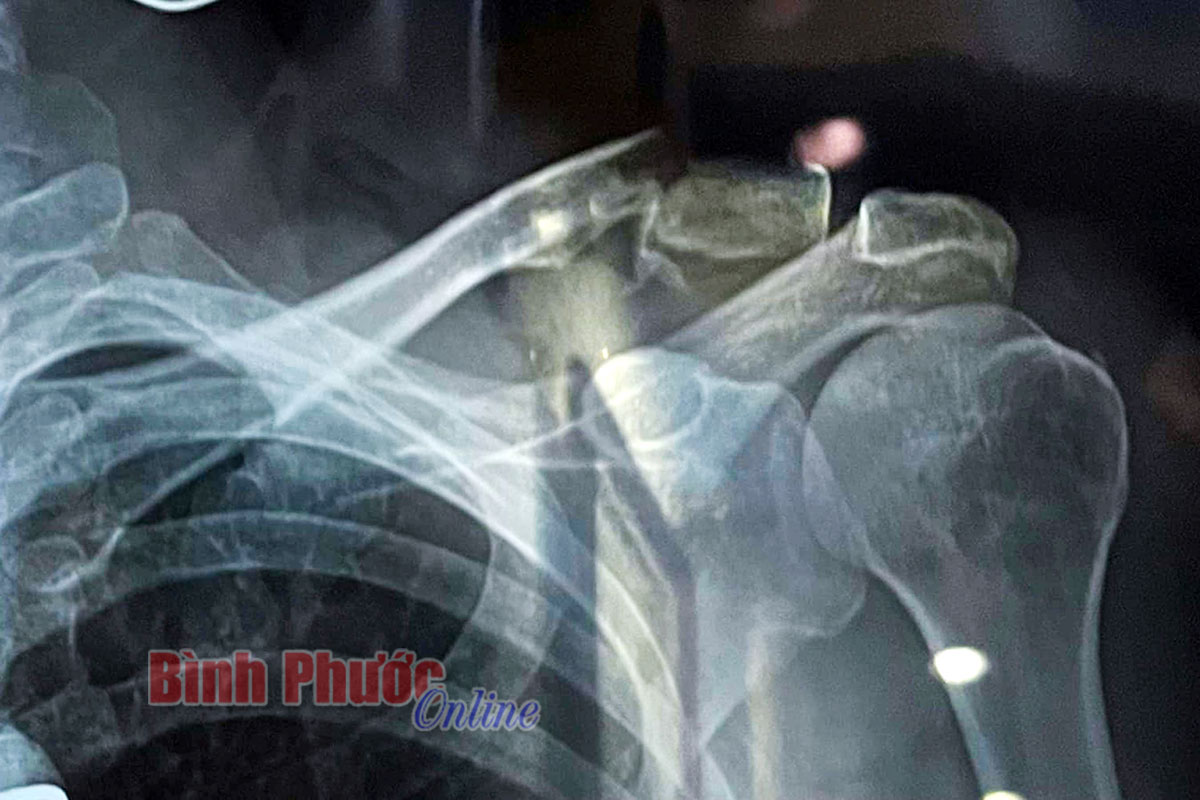

Theo hình ảnh chụp phim cho thấy, Javier Perez bị gãy xương đòn vai

Trên đường tập anh tránh đồng đội Nguyễn Thắng nên té ngã, dẫn đến gãy xương đòn vai. Theo tin từ CLB, anh đã được chuyển về TP. HCM để chuẩn đoán và phẩu thuật trong sáng nay 29-3. Nhiều khả năng anh phải dưỡng thương tối thiểu 1 tháng. Đây là một tổn thất rất lớn cho đội TP. HCM Vinama vì anh là Áo vàng mùa 2020.

Chấn thương khiến tay đua người Tây Ban Nha lỡ cơ hội tranh tài ở Cúp truyền hình HTV- Tôn Đông Á 2022